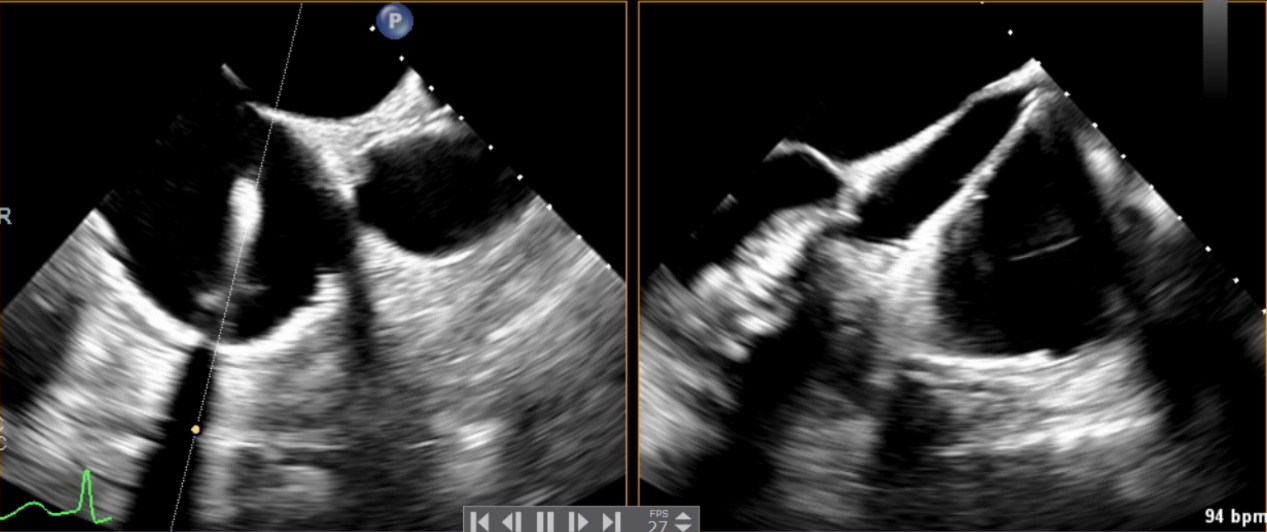

術(shù)中輸送器在超聲引導(dǎo)下調(diào)整位置

術(shù)后Azeem Latib教授對LuX-Valve Plus經(jīng)血管三尖瓣置換系統(tǒng)的器械性能和治療效果大為稱贊,并且認為LuX-Valve Plus的手術(shù)體驗非常好。從治療效果來看,術(shù)后即刻超聲顯示三尖瓣反流幾乎完全消失,血流動力學改善顯著,患者恢復(fù)快。在面對復(fù)雜解剖結(jié)構(gòu)、超聲影像質(zhì)量不佳、有起搏導(dǎo)線干擾時,Lux-Valve Plus也體現(xiàn)了極強的適應(yīng)性。Thomas Modine教授參與了術(shù)中指導(dǎo),他同樣再次肯定了LuX-Valve Plus術(shù)中操作的便捷性,認為LuX-Valve Plus容錯率高,對術(shù)中影像的依賴小,并表達了后期希望可以更多地應(yīng)用LuX-Valve Plus三尖瓣置換系統(tǒng)于臨床實踐,讓更多的三尖瓣重度反流患者盡早獲益,改善預(yù)后。